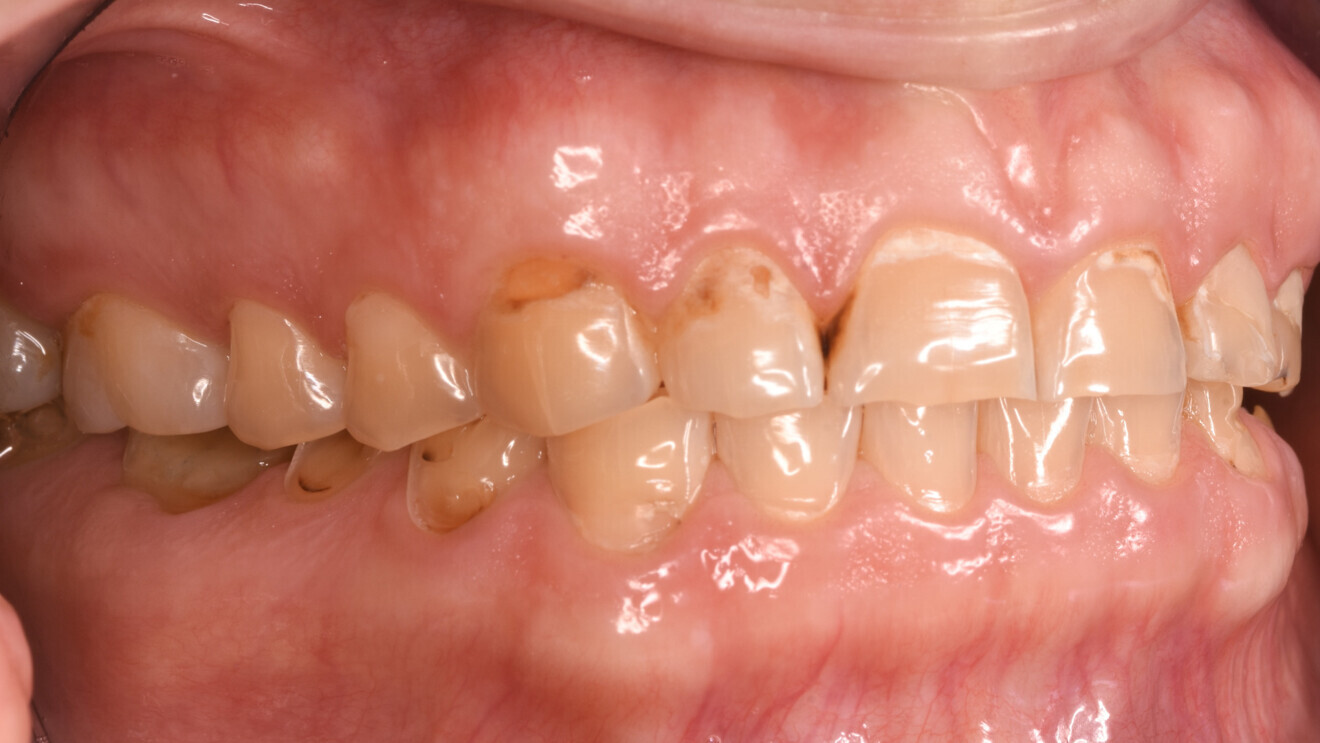

Fig. 1b: Initial situation. Left lateral view.

The clinical and radiographic examination revealed pronounced erosive defects on all teeth (Figs. 1a-f). To prevent nocturnal wear of the remaining tooth structure, an occlusal splint had been prepared by the patient’s general dentist in the past. Quick screening for temporomandibular disorder using the tool developed by the German Society of Craniomandibular Function and Disorders was carried out and revealed no functional abnormalities. The diagnosis was generalised, highly pronounced erosion due to exogenous acid (cola), abrasion and attrition with decreased OVD, multiple carious lesions, dentine hypersensitivity, gingivitis and compromised aesthetics.